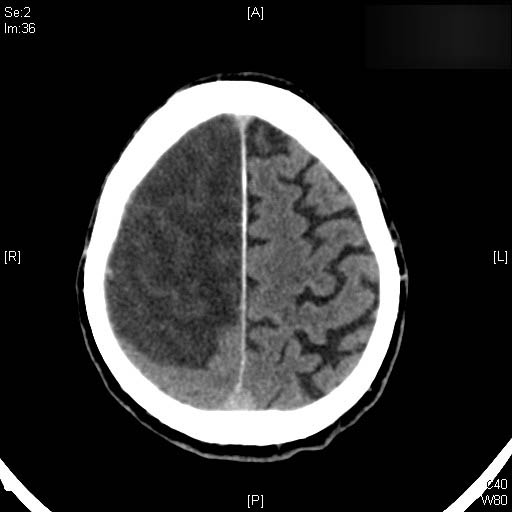

AVC amplio de territorio de A. cerebral media